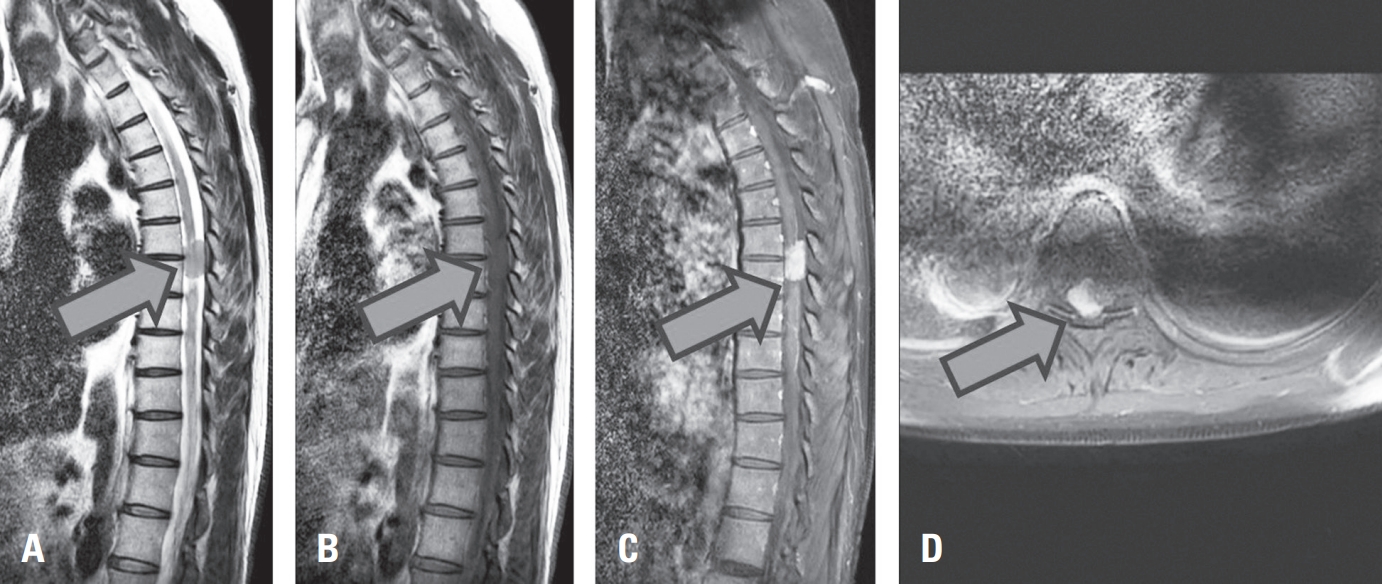

A yellowish, fragile tumor mass with a clearly defined margin from the medullary portion was exposed and subsequently removed en bloc (Fig.2. A, B).

Fig. 2.

Intraoperative findings and gross apprearance of the tumor. (A) Intraoperative view showing the exposed yellowish, fragile tumor material following dural and pial incision. (B) The tumor mass was removed en bloc, demonstrating its soft and well-demarcated appearance.

Fig. 2. Intraoperative findings and gross apprearance of the tumor. (A) Intraoperative view showing the exposed yellowish, fragile tumor material following dural and pial incision. (B) The tumor mass was removed en bloc, demonstrating its soft and well-demarcated appearance.